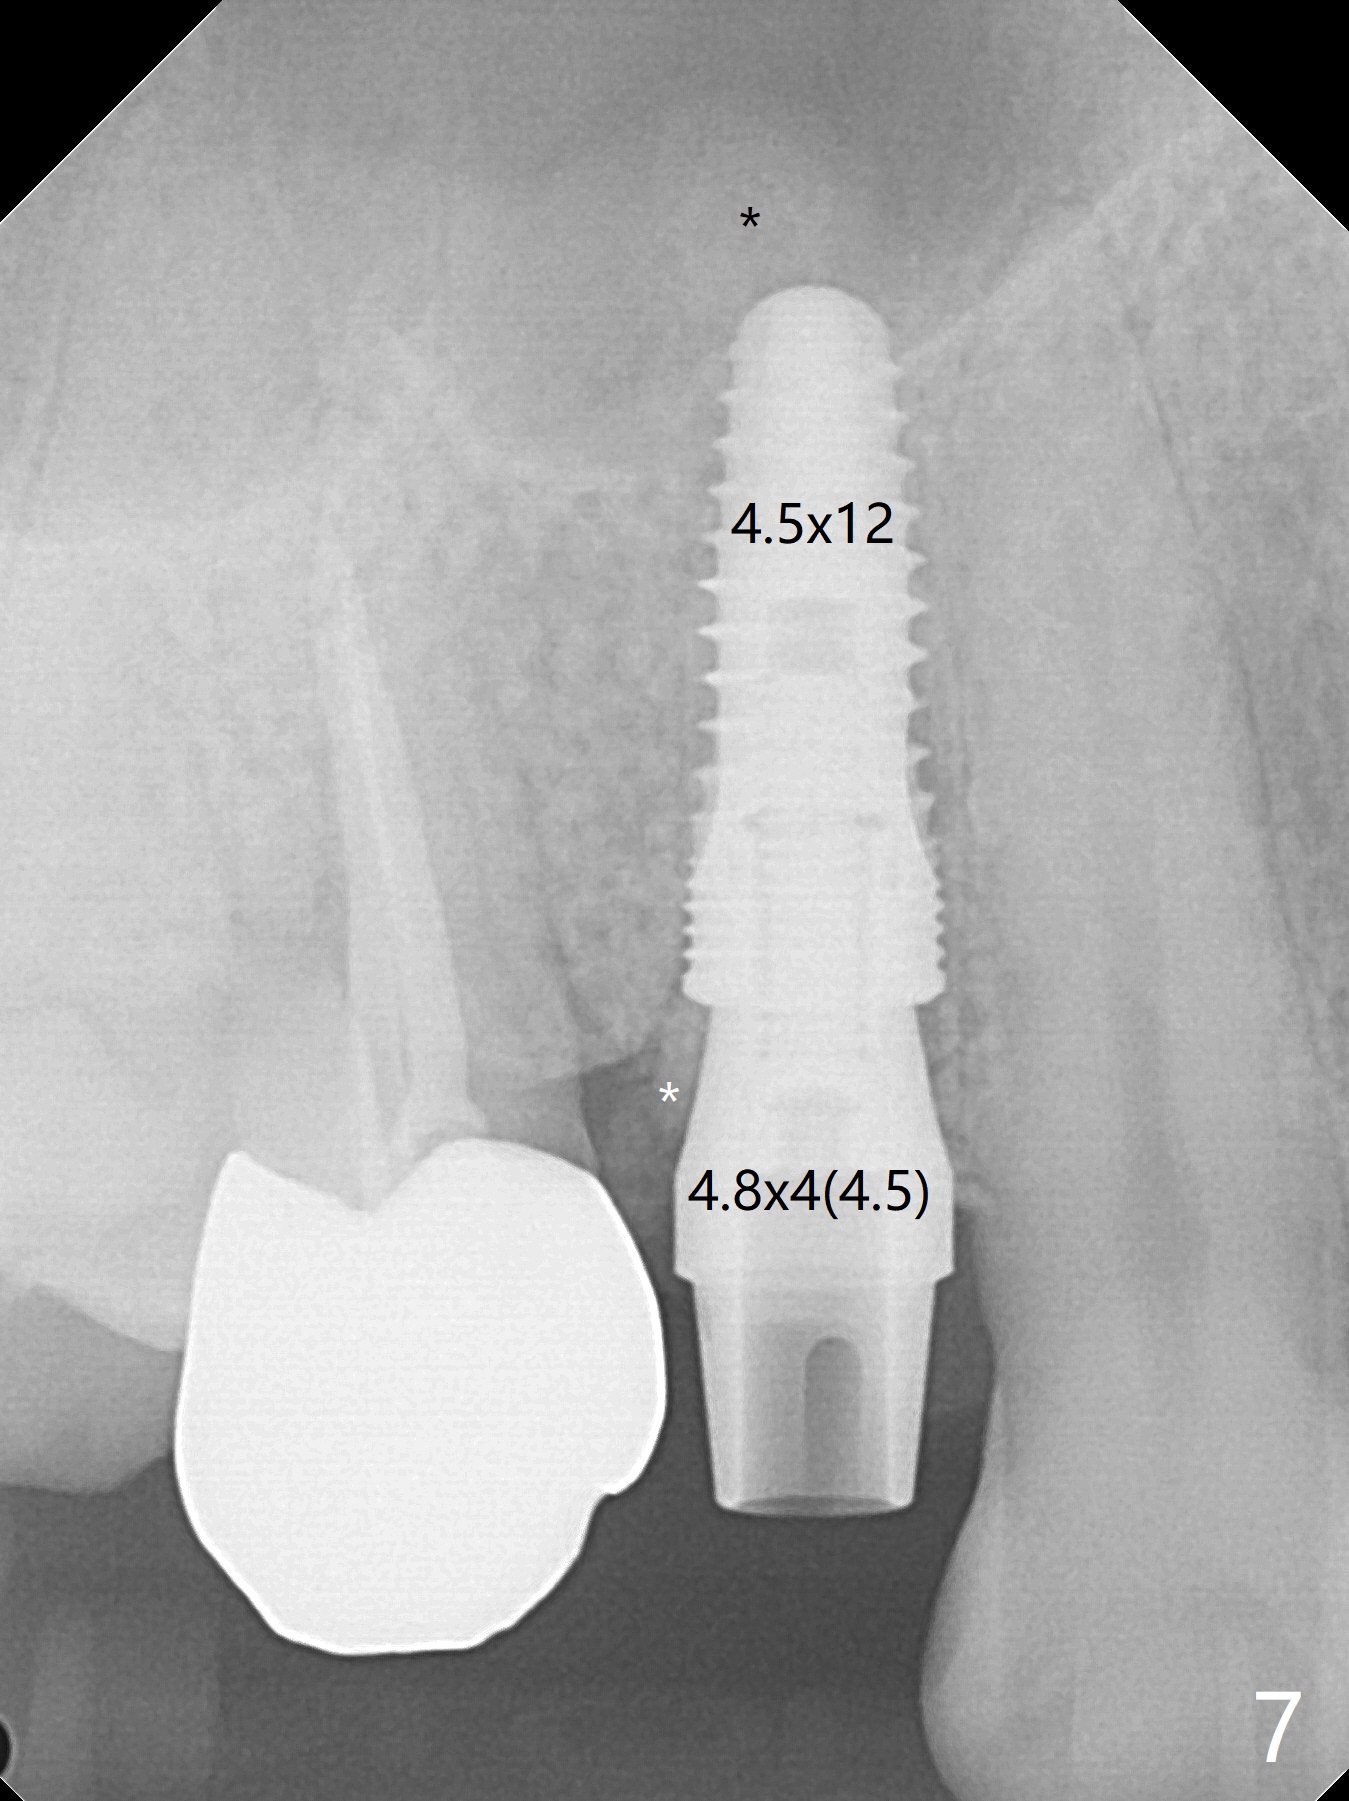

The buccal plate is normal at the tooth #5 (Fig.1) with the loose palatal fragment (Fig.2 P). Extraction leads to root fracture. Sectioning removes the palatal portion of the root and keeps the buccal semilunar piece (Fig.3 *); the mesiopalatal plate is resorbed (P). Initial osteotomy is off (Fig.4 (R: remaining root)). Redirection improves the trajectory (Fig.5). With the 2nd redirection (Fig.6 (4.5 mm tap)), a 4.5x12 mm implant is placed with 50 Ncm and sinus lift (Fig.7 black *); bone graft is placed with emphasis on the palatal defect (white *). As usual, an immediate provisional is fabricated. In fact the abutment may be not completely seated because of contact with the mesial crest. Prepare anesthetic and 5.5 mm profile drill. Take parallel BW or PA. Take occlusal photos to show no buccal or mesiopalatal atrophy. After 5.5 mm profile drill 11 months postop, the abutment has no contact with the mesial crest (Fig.8 <). Since the proximal contact between #3 and 4 is light with food impaction, the provisional at #5 is fabricated with tight distal contact. When the patient returns for final crown cementation (Fig.9), the food impaction is minimal between #3 and 4. The distal black triangle (Fig.10 *) and exposure of the abutment margin (^) are partially related to provisional fabrication and should dissolve over time considering socket shield.